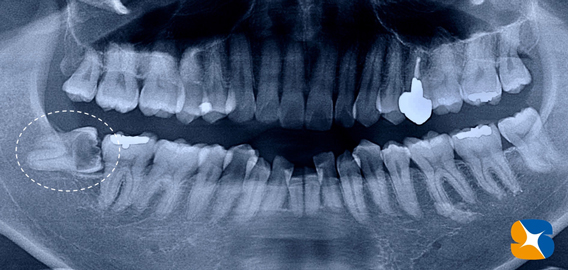

レントゲンからも大きな虫歯を確認。本日、昼休み中にインプラント手術があります。それが終わり次第抜歯を行うことにしました。

歯の上半分が虫歯のため、崩壊していましたので難しい抜歯になりましたが、無事に終えることができました。